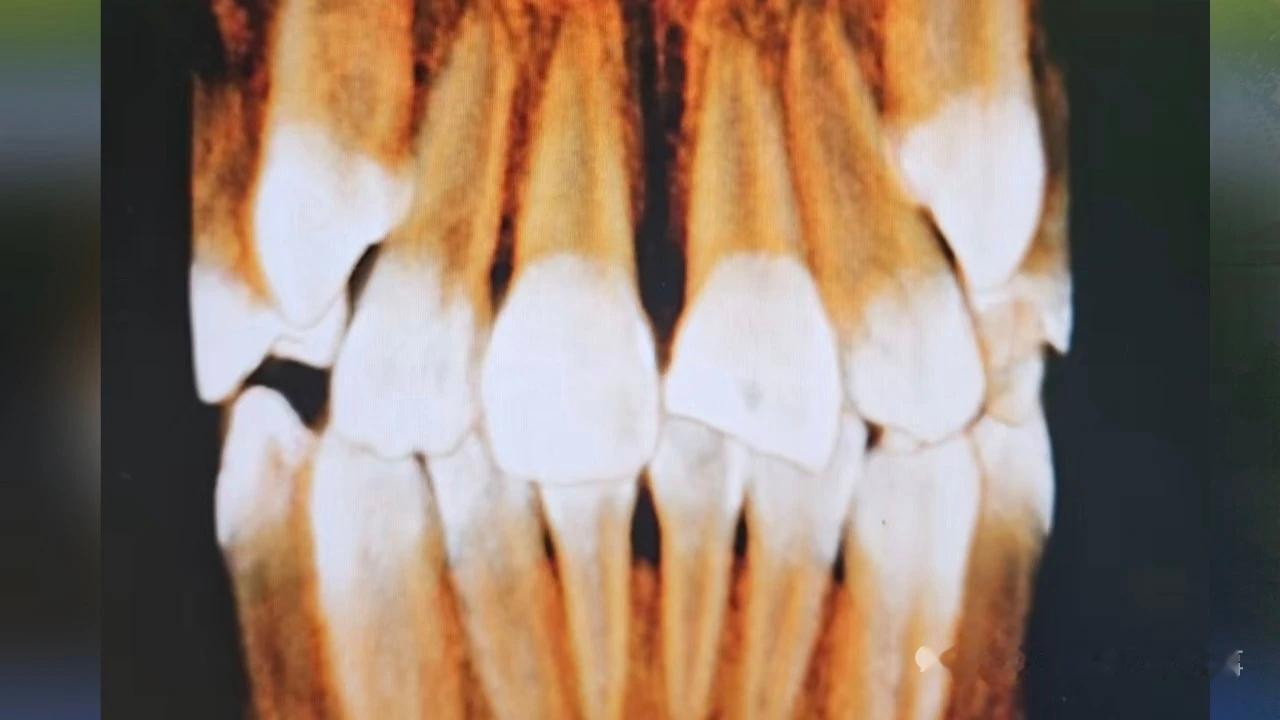

9岁女孩在游乐场摔断门牙,经营者和监护人谁该担责? 10月7号那天,山东省潍坊市张女士带孩子来到名为星高度亲子乐园的游乐场,孩子在玩蹦床的时候不小心摔倒磕到了旁边的铁围栏。孩子摔倒后,立刻捂着嘴站起来,向蹦床的一边走去,不远处的张女士也赶紧迎过来查看孩子的伤势。 经过医生检查诊断为创伤性牙折断,医嘱中明确写明预后效果无法估计,后期可能出现牙髓坏死、牙齿内吸收、外吸收、牙齿松动、根尖囊肿等情况,可导致牙齿无法保留,需长期随诊观察。也正是这些不可预知的后果,让张女士非常担心。 张女士的孩子今年9岁,门牙已经更换,虽然目前的治疗费不算多,但如果牵涉到后期的补牙或种牙,则是一笔不小的开销。事后,张女士也咨询过医生,如果孩子成年后需要补牙或种牙,大概需要6000元—8000元的治疗费。 张女士认为,像蹦床这样的游乐设施,因为会有身体腾空的状态,游玩者无法完全控制身体,两侧应设置网状或柔软的安全防护措施,现场的铁栏杆极易造成二次伤害。即便当时自己就在离孩子不远的地方,但意外发生的太突然,孩子一旦摔倒,家长也来不及制止,因此张女士向游乐场提出了一万元的赔偿诉求。 对于张女士提出的赔偿要求,亲子乐园一方又是什么态度呢? 潍坊星高度亲子乐园的负责人解释,游乐园已经开业一年半,从开园至今因为蹦床磕到牙的孩子这是头一个,而且当天是因为下雨湿滑,才出了这个意外。对于责任问题,游乐园倒不回避,负责人说他们购买了公众责任险,目前保险公司正在评估赔付范围和赔付额度。 对于工作人员的说法,张女士提出了两点担心:一是担心场地搬走后找不到负责人。二是担心孩子成年后的种牙或补牙费用,不在保险理赔范围内。 针对张女士的担心,工作人员也做出了解释。如果有超出保险公司保险范围的费用,建议张女士通过法律程序明确责任划分,需要公司承担的部分他们会根据责任比例承担。 未成年人在公共场合意外受伤,经营者与监护人如何划分责任比例? 对于尚未发生但又可能有需求的医疗费用,伤者又该如何主张? 齐鲁频道法律服务团律师 徐江涛:公共场所的管理者要尽到安全保障义务,如设置安全保障设施、张贴安全标识、场所内有安保人员,警示标识里列明需家长陪同等,这些可以证明商家尽到了安全保障义务,但不能完全免责。9岁半的儿童属于限制民事行为能力人,意外发生时有监护人在场,作为监护人应知悉游乐场所的游戏规则、安全注意防范措施,如监护人对未成年的孩子未尽到看护义务也应承担部分责任。 对于已经产生的医疗费,伤者可要求游乐场进行赔付。对于未产生但可能有医疗需求的费用,需双方协商,建议家长完善病历,通过医嘱或医学手段对意外与牙齿更换的因果关系进行鉴定。 在双方约定时间内,亲子乐园与张女士就赔偿事宜达成一致:由保险公司赔付张女士5000元,亲子乐园赔偿2000元,张女士对这一赔偿方案表示接受。 来源 小溪办事